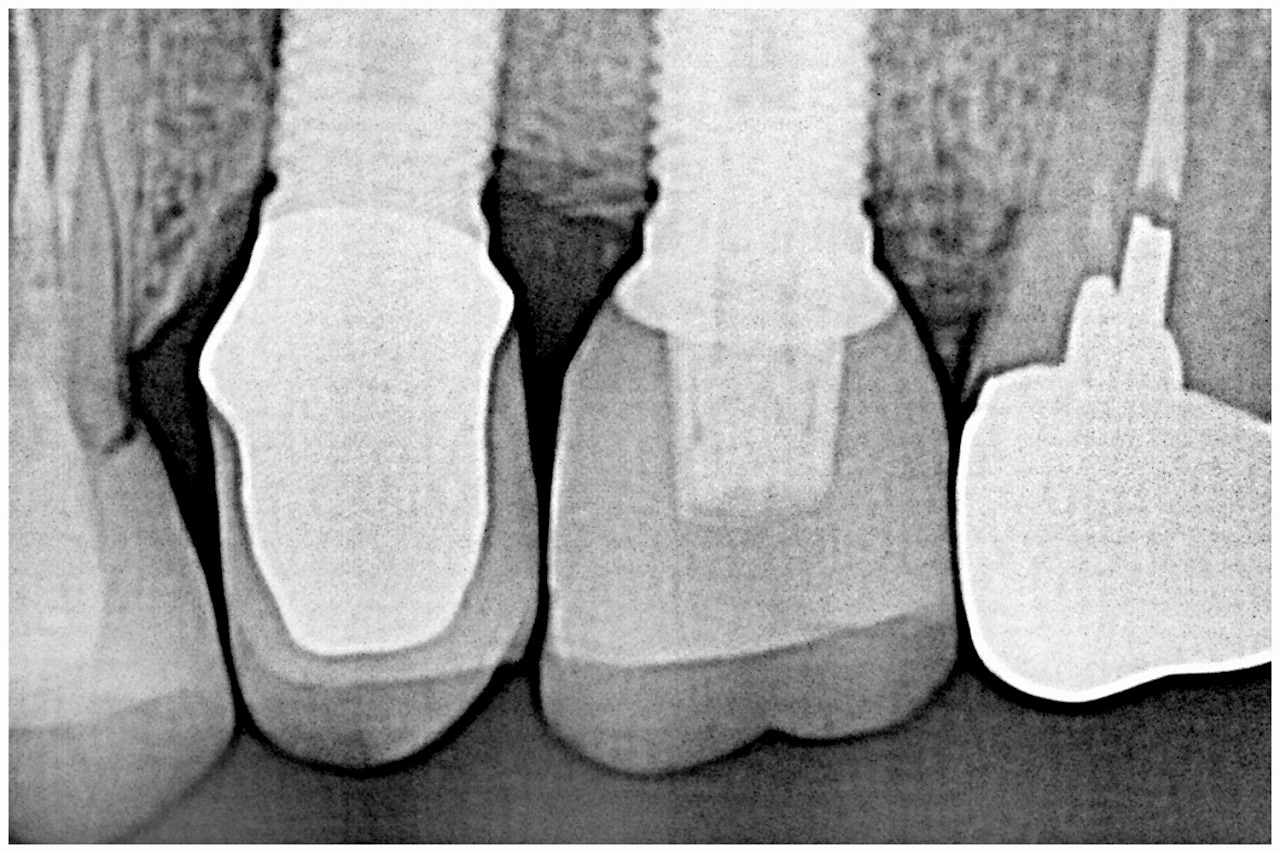

カスタムのアバットメントを建てていきました

その上にオールセラミッククラウンを合わせていきます

このように綺麗に仕上がりました

機能時のデンタルレントゲンになります